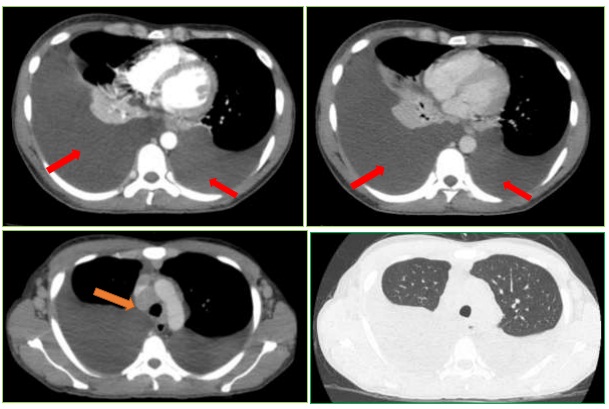

Hình ảnh Cắt lớp vi tính lồng ngực trước điều trị:

Hình 1: Tràn dịch màng phổi (mũi tên đỏ) 2 bên số lượng lớn (bên phải dày 94mm, bên trái dày 71mm) gây xẹp phổi 2 bên. Hạch to trung thất và rốn phổi 2 bên, lớn nhất 20x27mm (mũi tên cam). Gan to, lách to.